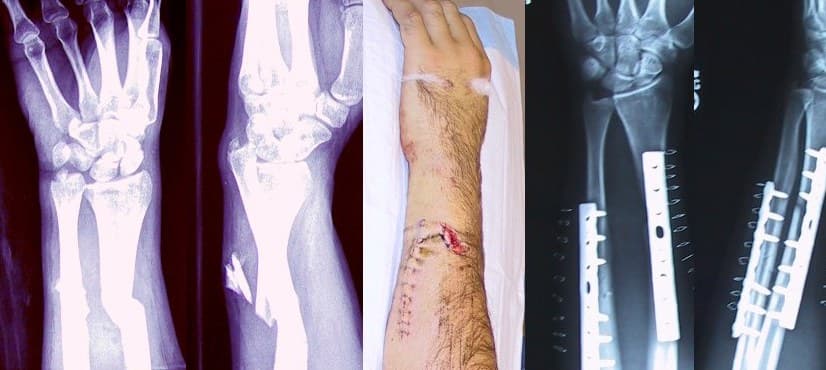

A bone fracture (abbreviated FRX or Fx, Fx, or #) is a medical condition in which there is a partial or complete break in the continuity of any bone in the body. In more severe cases, the bone may be broken into several fragments, known as a comminuted fracture. A bone fracture may be the result of high force impact or stress, or a minimal trauma injury as a result of certain medical conditions that weaken the bones, such as osteoporosis, osteopenia, bone cancer, or osteogenesis imperfecta, where the fracture is then properly termed a pathologic fracture. Although bone tissue contains no pain receptors, a bone fracture is painful for several reasons: Breaking in the continuity of the periosteum, with or without similar discontinuity in endosteum, as both contain multiple pain receptors. Edema and hematoma of nearby soft tissues caused by ruptured bone marrow evokes pressure pain. Involuntary muscle spasms trying to hold bone fragments in place. Damage to adjacent structures such as nerves, muscles or blood vessels, spinal cord, and nerve roots (for spine fractures), or cranial contents (for skull fractures) may cause other specific signs and symptoms. Some fractures may lead to serious complications including a condition known as compartment syndrome. If not treated, eventually, compartment syndrome may require amputation of the affected limb. Other complications may include non-union, where the fractured bone fails to heal, or malunion, where the fractured bone heals in a deformed manner. One form of malunion is the malrotation of a bone, which is especially common after femoral and tibial fractures. Complications of fractures may be classified into three broad groups, depending upon their time of occurrence. These are as follows – Immediate complications – occurs at the time of the fracture. Early complications – occurring in the initial few days after the fracture. Late complications – occurring a long time after the fracture. Bone healing The natural process of healing a fracture starts when the injured bone and surrounding tissues bleed, forming a fracture hematoma.